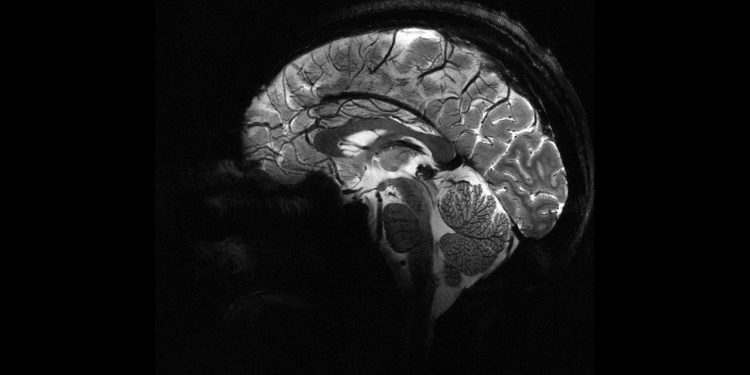

Epilepsiye farklı nedenler yol açsa da, vakaların yaklaşık yüzde 30’u beyindeki yapısal anormalliklerden kaynaklanıyor. Ancak bu lezyonlar, özellikle de beynin kıvrımlarının derinliklerinde saklı olan en küçük olanlar, çoğu zaman MR görüntülerinde fark edilmiyor.

Melbourne Kraliyet Çocuk Hastanesi’nden pediatrik nörolog Emma Macdonald-Laurs liderliğindeki ekip, çocuk beyin görüntüleri üzerinde yapay zekâ modeli eğiterek yaban mersini büyüklüğünde ya da daha küçük lezyonları ortaya çıkarmayı başardı.

“Bu lezyonlar sıkça gözden kaçıyor ve birçok çocuk cerrahi adayları arasına alınmıyor. Araç radyologların ya da epilepsi uzmanlarının yerini almıyor ama adeta bir dedektif gibi ipuçlarını hızla birleştirerek tedavi sürecini hızlandırıyor,” dedi Macdonald-Laurs.

Araştırmada kortikal displazi ve fokal epilepsi hastaları üzerinde testler yapıldı. Daha önce MR sonuçları “normal” raporlanan bu çocukların yüzde 80’inde aslında gizli lezyonlar olduğu belirlendi.

Yapay zekâ aracı hem MR hem de PET taramalarını analiz ettiğinde, bir test grubunda yüzde 94, diğerinde yüzde 91 başarı oranı yakaladı. İlk gruptaki 17 çocuktan 12’si beyin lezyonlarının çıkarılması için ameliyat edildi ve 11’i artık nöbetsiz yaşıyor.